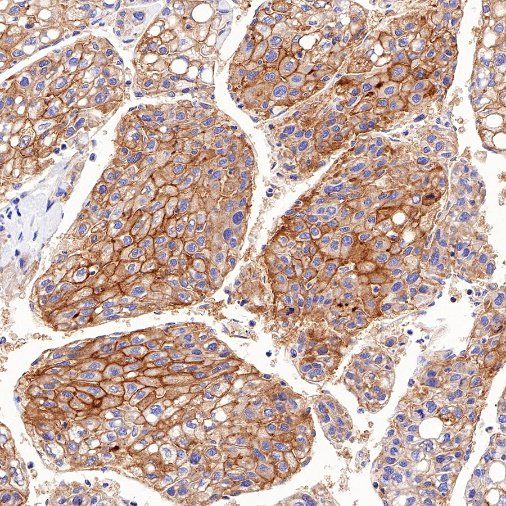

Immunohistochemistry

IHC shows positive staining in paraffin-embedded human kidney. Anti-MDR1/ABCB1 antibody was used at 1/1000 dilution, followed by a HRP Polymer for Mouse & Rabbit IgG (ready to use). Counterstained with hematoxylin. Heat mediated antigen retrieval with Tris/EDTA buffer pH9.0 was performed before commencing with IHC staining protocol.